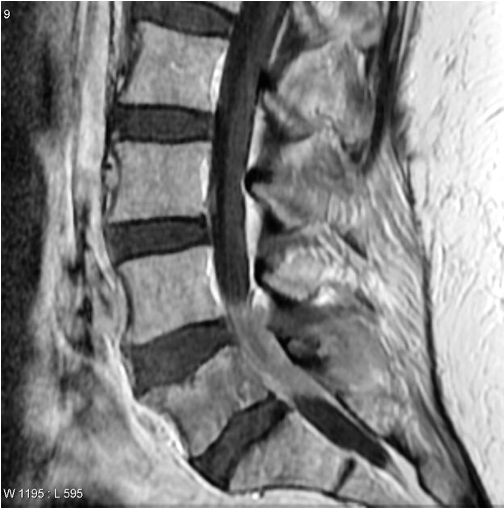

Spine Synovial Cysts MRI

Extramedullary Intradural

- dermoid

- epidermoid

- meningioma

- neurofibroma